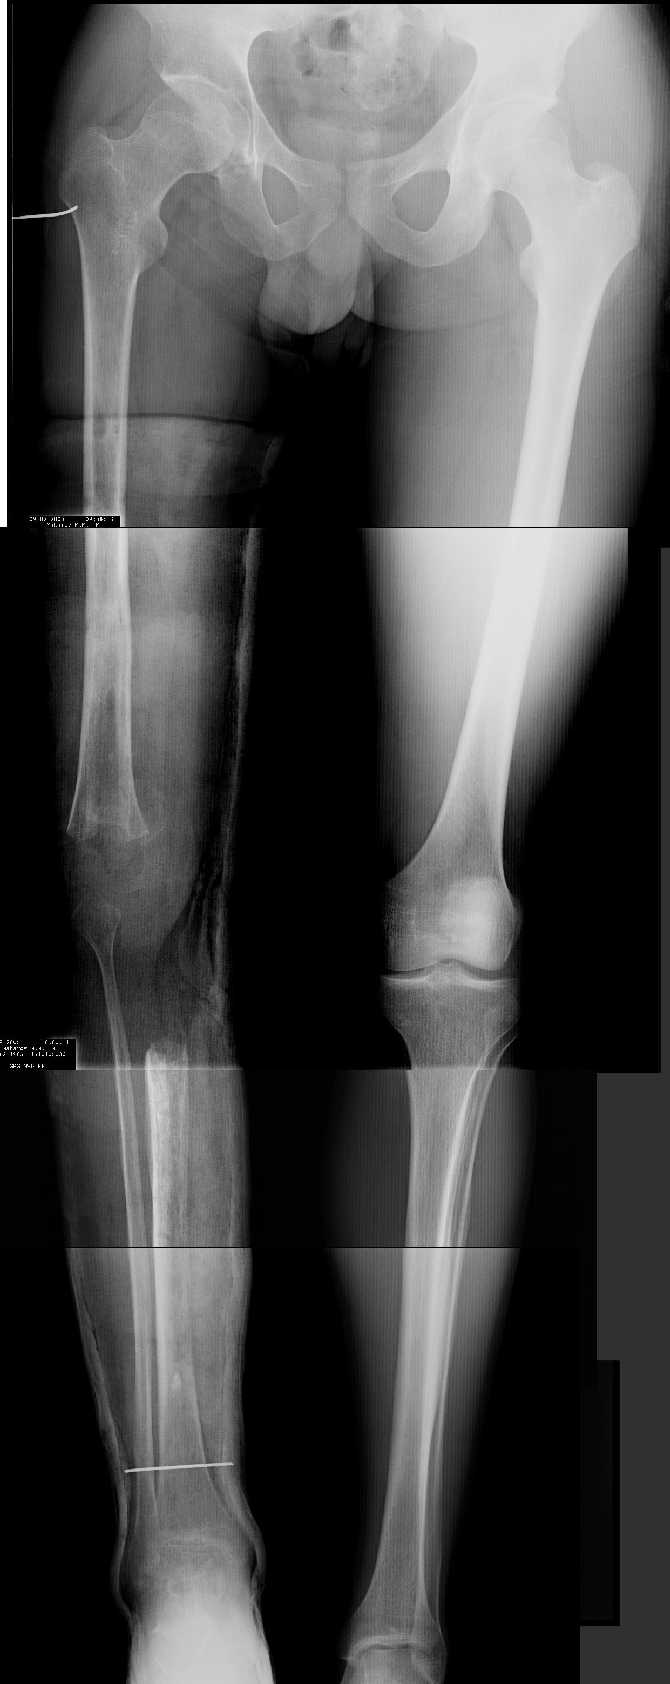

2. Другой пример - дефект после инфицирования коленного эндопротеза.

Предполагалось, что величина дефекта 11-12 см. Так получается, если

сделать снимок только области коленных суставов. Определить

укорочение сложно, так как нога просто болтатется.

Сделали снимок "от и до" - величина дефекта 17 см.

Правда эта иллюстарция сделана на цифровом рентгеновском аппарате.

Больной стоит, а трубка передвигается сверху вних, последовательно

выполняя рентгенограммы. В данном случае - 4 штуки.